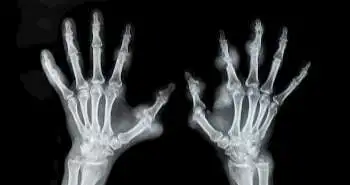

Sarcopenia is described by the muscle strength and mass loss, following falls and adverse health issues. The study intended to evaluate sarcopenia prevalence among rheumatoid arthritis (RA) patients and assess factors correlated with sarcopenia.

A cross-sectional analysis with 388 consecutive RA women was conducted. The assessment of bone fractures and falls maintained above the previous year was done. Logistic regression analyses were used to assess sarcopenia association with RA characteristics, falls, and bone fractures.

The 37.1% prevalence was noticed for sarcopenia with 49.0% of low muscle mass. The RA patients with sarcopenia presented high rates of fractures, low bone mineral density and falls. The independent factors noticed to be related with sarcopenia were Steinbrocker’s stage, use of biological disease-modifying antirheumatic drugs (bDMARDs), the high Mini-Nutritional Assessment-Short Form score, age, and RA duration.